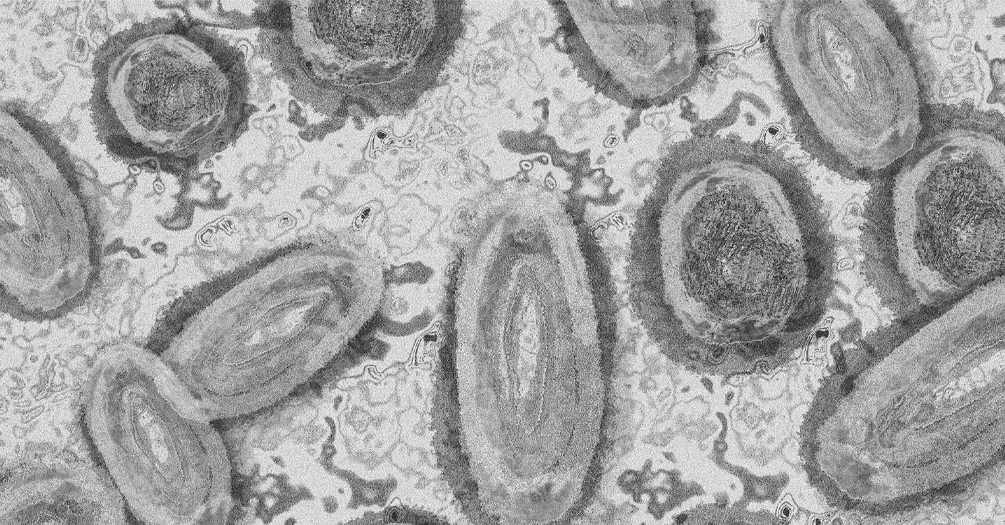

How concerned should you be about mpox?

Mpox, a virus that causes pus-filled blisters, has been detected in several countries, including the United States, Canada, Australia and some European nations.